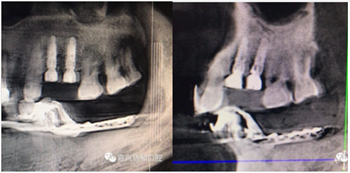

術(shù)后種植體位置與術(shù)前設(shè)計一致

3D數(shù)字化種植導(dǎo)板的臨床應(yīng)用,顛覆了以往以經(jīng)驗(yàn)判斷的粗放型的種植模式。

3D數(shù)字化種植導(dǎo)板的臨床應(yīng)用,是將種植牙精準(zhǔn)的種植于缺牙位點(diǎn),避免了臨近牙及重要器官的損傷、縮短了手術(shù)時間、減少了手術(shù)創(chuàng)傷,為缺失牙的咀嚼功能重建、外在形態(tài)恢復(fù)提供了保障。